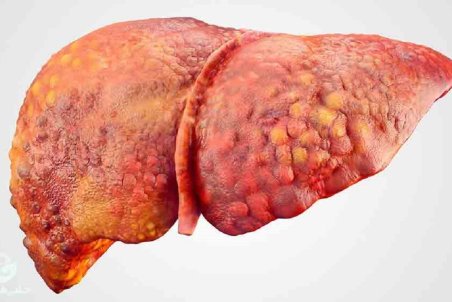

بیماری کبد چرب به معنی انباشت چربی در سلولهای کبد بوده البته طبیعی است که چربی در کبد داشته باشید، اما وقتی که چربی بیش از ۵ تا ۱۰ درصد در کبد وجود داشته باشد، در این صورت فرد به بیماری کبد چرب مبتلاست.

کبد ۲۰ درصد ایرانی ها چرب است/دومیلیون نفر گرفتار هپاتیت B و C

شیوع ۲۰ تا ۳۰ درصدی کبدچرب در ایران